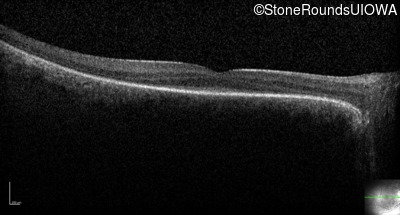

Optical Coherence Tomography - Right - Light Perception

Exemplar / OCT Stack